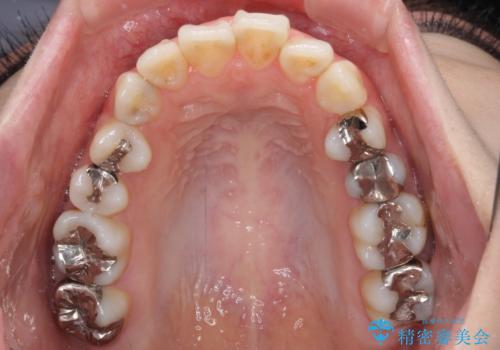

- 口元の突出感と奥歯の欠損を気にして来院された患者様です。

口元の突出感改善には、上下左右の第一小臼歯4本を抜歯し、奥歯の欠損部には矯正治療の途中でインプランを埋入していくこととしました。